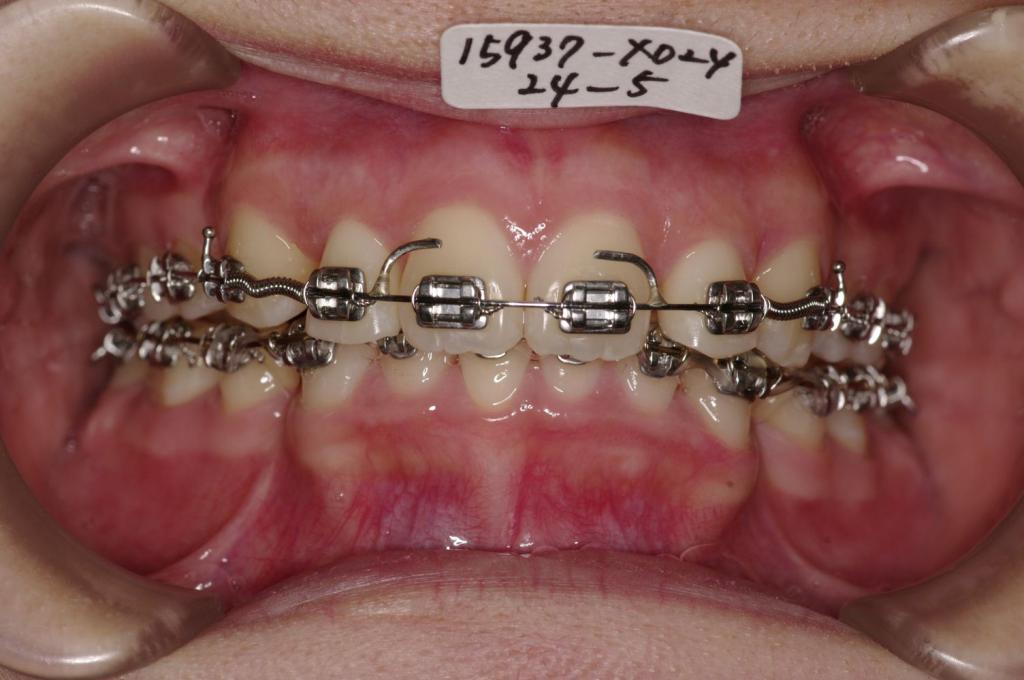

装置の種類及び治療法 診断:叢生

治療方法および装置:マルチブラケット装置

High pull J-hook headgear

抜歯:右上4 /左上4

右下84 /左下48

欠損歯:右上 /左上8

装置写真

治療前

歯並び・咬み合わせ・八重歯・乱杭歯の矯正治療前口内写真NO.1225